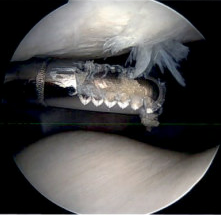

Microfracture

Microfracture of trochlea chondral defect